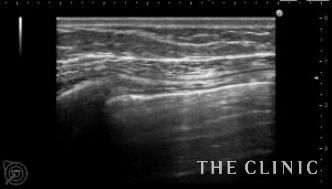

本日紹介する方は左胸の痛みで来院、見た目や触診では問題ありませんでしたが、エコー検査で左胸のバッグが破損していました。エコー所見です。右は軽度のカプセル拘縮を認めますが、左は破損してカプセル内にシリコンが漏れていました。腋の下からバッグを取り出しましたが、左のカプセル内にはシリコンが漏れていました。

バッグの破損があると術後にカプセル内にリンパ液が貯留する場合がありますが、

1週間後のエコーではリンパ液の貯留もなく問題ありませんでした。バッグの破損は自覚症状がない場合も多いので、定期的にエコー検査をするべきだと思います。